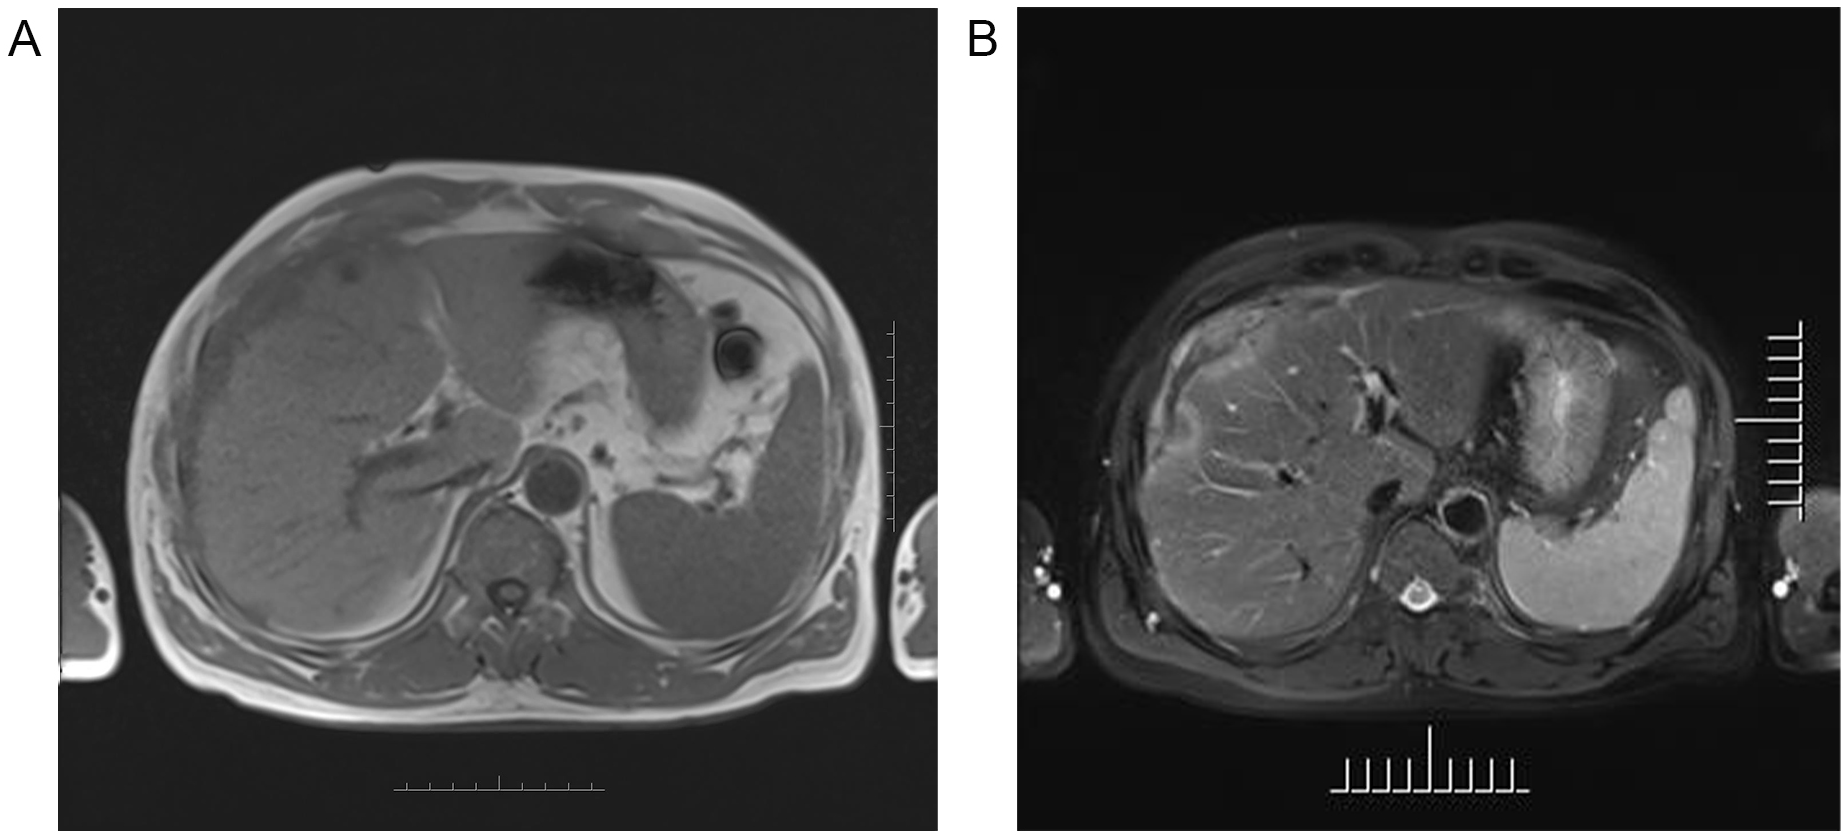

Figure 2

Axial MR images of the upper abdomen showing the lesion in the right subdiaphragm and right anterior and left medial lobe of the liver demonstrated intermediate-to-low intensity on T1-weighted images (A), and central intermediate-to-low intensity and peripherally intermediate-to-high signal on T2-weighted image (B).

Ultrasound (US) imaging revealed an ill-defined, heterogeneous, hypoechoic lesion involving the right subdiaphragm as well as the right anterior and left medial lobes of the liver. The hepatic parenchyma showed diffuse heterogeneity without distinct nodules. Thoracic computed tomography (CT) scans demonstrated an elevated right diaphragm, bilateral pleural thickening, and bilateral diaphragmatic pleural calcifications, along with enlarged anterior mediastinal lymph nodes. No significant pulmonary masses were identified. Abdominal contrast-enhanced CT images in the late arterial phase revealed multiple nodular and sheet-like low-attenuation lesions with peripheral enhancement in the right subdiaphragm, right anterior, and left medial lobes of the liver (Figure 1). These lesions showed “washout” in the portal vein and late phases. Enhanced nodules were observed in the peritoneum around the liver and in the fat septa of the ascending colon. Based on thoracic CT findings, the common primary malignancies were excluded, including masses in the lung, pancreas, spleen, kidneys, ureters, and prostate. Magnetic resonance (MR) imaging indicated intermediate-to-low intensity lesions on T1-weighted images (T1WI) and central intermediate-to-low intensity with peripheral intermediate-to-high signal intensity on T2-weighted images (T2WI). Diffusion-weighted imaging revealed restricted diffusion (Figure 2). No significant retroperitoneal abnormalities were noted. An 18-fluorodeoxy-glucose positron emission tomography with CT (18F-FDG PET/CT) scan revealed abnormally elevated FDG uptake in the poorly defined low-attenuation lesions in the right subdiaphragm and right anterior and left medial lobes of the liver, with a maximum standardized uptake value (SUVmax) of 11.2. Additional FDG activity was noted in the right peritoneum with irregular nodular thickening (SUVmax 7.7) and multiple hypermetabolic nodules in the right abdominal cavity, the largest of which had an SUVmax of 11.9 (Figure 3). No abnormal FDG uptake was observed in the lungs. An ultrasound-guided biopsy of the right subdiaphragmatic lesion and hepatic mass revealed dense fibrocollarous tissue invasion by atypic tumoral cells with spindle, triangular, or polygonal-shaped and hyperchromatic nuclei, involving both the peritoneum and liver (Figure 4). Immunohistochemical analysis showed these cells were positive for Ki-67 (20%), cytokeratin (CK) 7, WT-1, vimentin, CK (pan), D2-40 (weakly positive), and calretinin (CR), but negative for villin, CK20, and CDX-2. These findings supported a diagnosis of desmoplastic malignant peritoneal mesothelioma (DMPM). The patient underwent chemotherapy with pemetrexed and cisplatin and was discharged after completing the treatment.